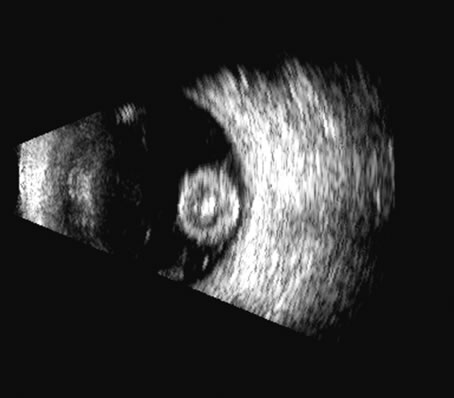

On B-scan, the invasion or replacement of the choroid by tumor is of diagnostic importance. Subretinal hemorrhage rests on a smooth curve of the posterior poles; whereas melanoma may replace the choroid, producing an “excavated” pattern.36 A completely dislocated lens can also emulate a tumor but can be differentiated by clinical findings and by having the patient move his or her eye during the examination, which causes lens displacement (Fig. 24).

Fig. 24. In this traumatized eye, the crystalline lens was completely dislocated and can be seen as a rounded mass in the posterior chamber, in a suitable plane.